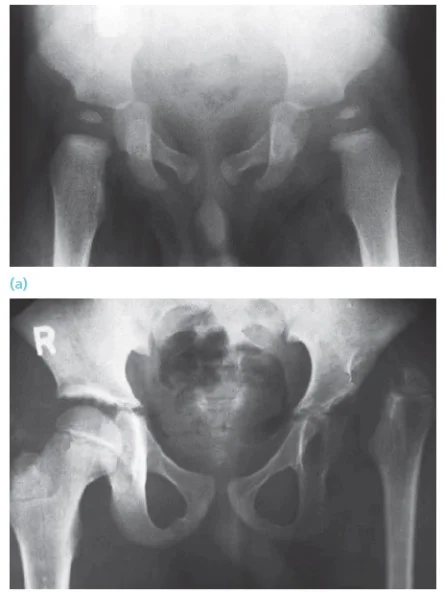

Case: septic arthritis, hip 14y old boy Presented with pain in R hip after history of a fall with abrasions few days before Had fever, limitation of R hip motion WBC: 13,000, ESR 23mm/1 hour Initial x-ray: not significant

Initial x-ray

X-ray 8 days later

X-ray taken on follow-up after surgical irrigation and debridement – too late!